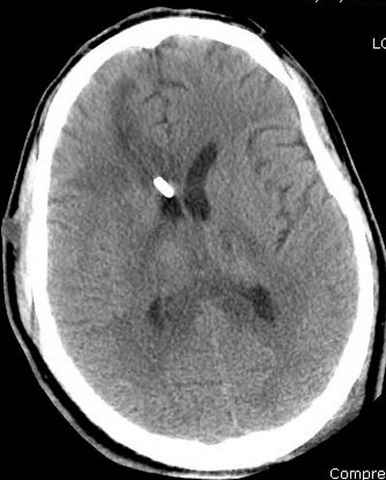

Наблюдается службой травмы и нейрохирургии (ICP) Increased Intracranial Pressure by ventricular cateter

больной без сознания, со слов нейрохирурга, наблюдается положительная динамика в нейрохирургическом статусе.

монииторинг